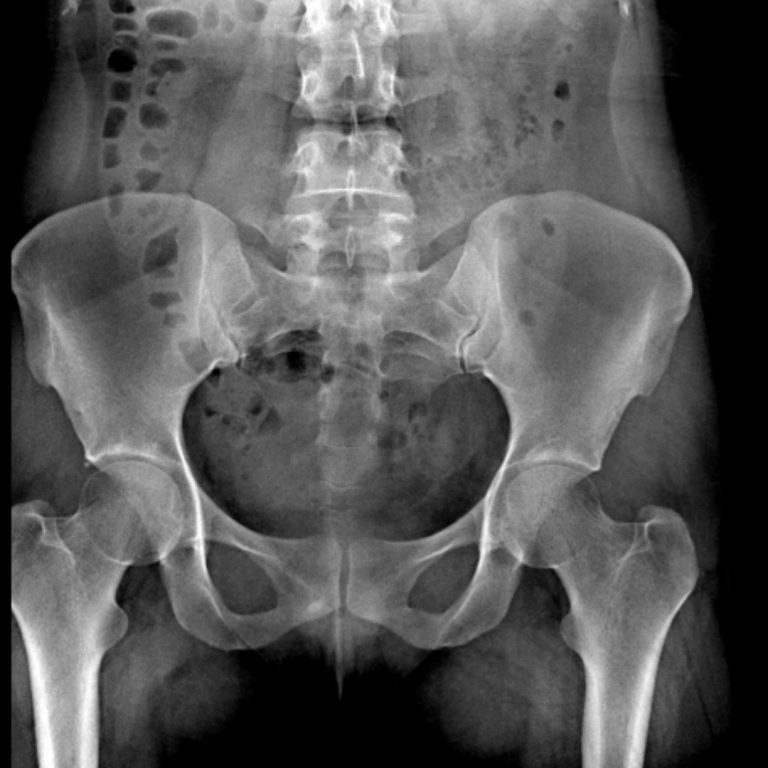

VOİDİNG SİSTOGRAFİ

Voiding Sistoüretrografi (VSUG) mesane ve alt üriner sistemin değerlendirilmesi için kullanılan bir X-ışını ile görüntüleme yöntemi olup mesaneye bir sonda ile verilen kontrast madde aracılığıyla, işeme sırasında idrar yollarının görüntülenmesidir.Çocuklarda üriner sistem infeksiyonunu takiben vezikoüreteral reflü şüphesi varlığında VSUG incelemesine gerek duyulmaktadır.

Voiding sistoüretrografi nasıl yapılır ?

Radyoloji teknisyeni çocuğunuzu inceleme masasına yerleştirdikten sonra çocuğun hareketini engelleyici araçlar kullanabileceği gibi sizden de çocuğu tutma konusunda yardım isteyebilir. Kontrast madde verilmeden önce mesane boşken bir film çekilir. Daha sonra özel bir sıvıyla çocuğunuzun cinsel organını temizlenir ve mikropsuz bir ortam sağladıktan sonra ince bir kateter (ince, esnek bir tüp) idrar yolundan geçirerek mesaneye yerleştirilir. Tüpün ucu kontrast madde içeren bir torbaya bağlanarak yerçekiminin etkisiyle mesane tamamen dolana kadar beklenir.

Mesane dolarken mesaneden üst idrar yollarına kaçış olup olmadığına bakılarak çeşitli filmler çekilir. Mesane tamamen dolduğunda sonda çıkartılır ve çocuk idrarını yaparken seri filmler çekilir.İşeme sona erdiğinde mesanede idrar kalıp kalmadığını görebilmek için bir film daha çekilerek işlem sonlandırılır. İşlem ağrısız olmakla beraber küçük çocuklar hareketleri engellendiğinde ağlayabilmektedirler. Kateter takılmadan önce çocuğunuzun cinsel bölgesi mikroplardan arındırmak için özel bir sıvıyla temizlenir. Bu sıvı soğukluk hissi oluşturabilir. Kateterin takılması ve mesanenin kontrast madde ile doldurulması ağrısız olmakla beraber bazı çocuklar rahatsızlık hissedebilirler. Çocuğunuzun korkmaması ve sakinleşmesi için, radyasyona maruz kalabileceğinizden kurşun önlük giyme şartı ile çekim süresince yanında kalabilirsiniz. Tüm işlemler, yaklaşık 15 dakikada tamamlanır.